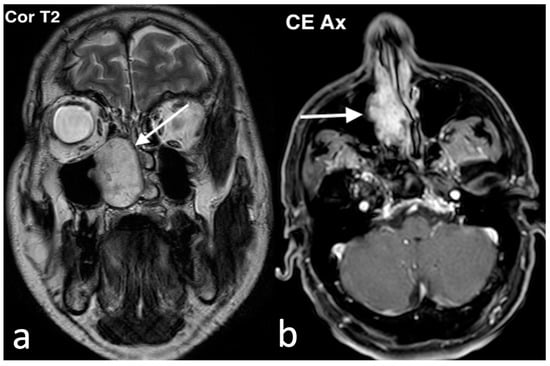

3.2.2. Chondromesenchymal Hamartoma